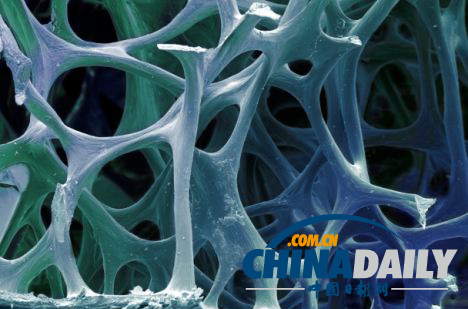

研究人員將皮膚細胞重新編排成能夠形成早期階段骨細胞的干細胞,圖為骨細胞內部的海綿狀結構。

研究人員首先將皮膚細胞重新編排成干細胞,這種干細胞能夠形成早期階段的骨細胞,然后再將其接種到三維支架中,同時提供營養刺激其生長。在經過長達12周的培養后,這種由皮膚細胞轉化而來的骨細胞被移植到實驗鼠體內,并順利形成了骨組織。在整個實驗過程中,沒有出現任何可能產生腫瘤的現象。

“骨骼是一種非常活躍的器官,會不斷進行重塑,”馬洛特博士說道,“血液能為健康細胞提供營養并帶走代謝廢物,神經能將其與大腦相連接,骨髓細胞則能形成新鮮的血液和免疫細胞。”